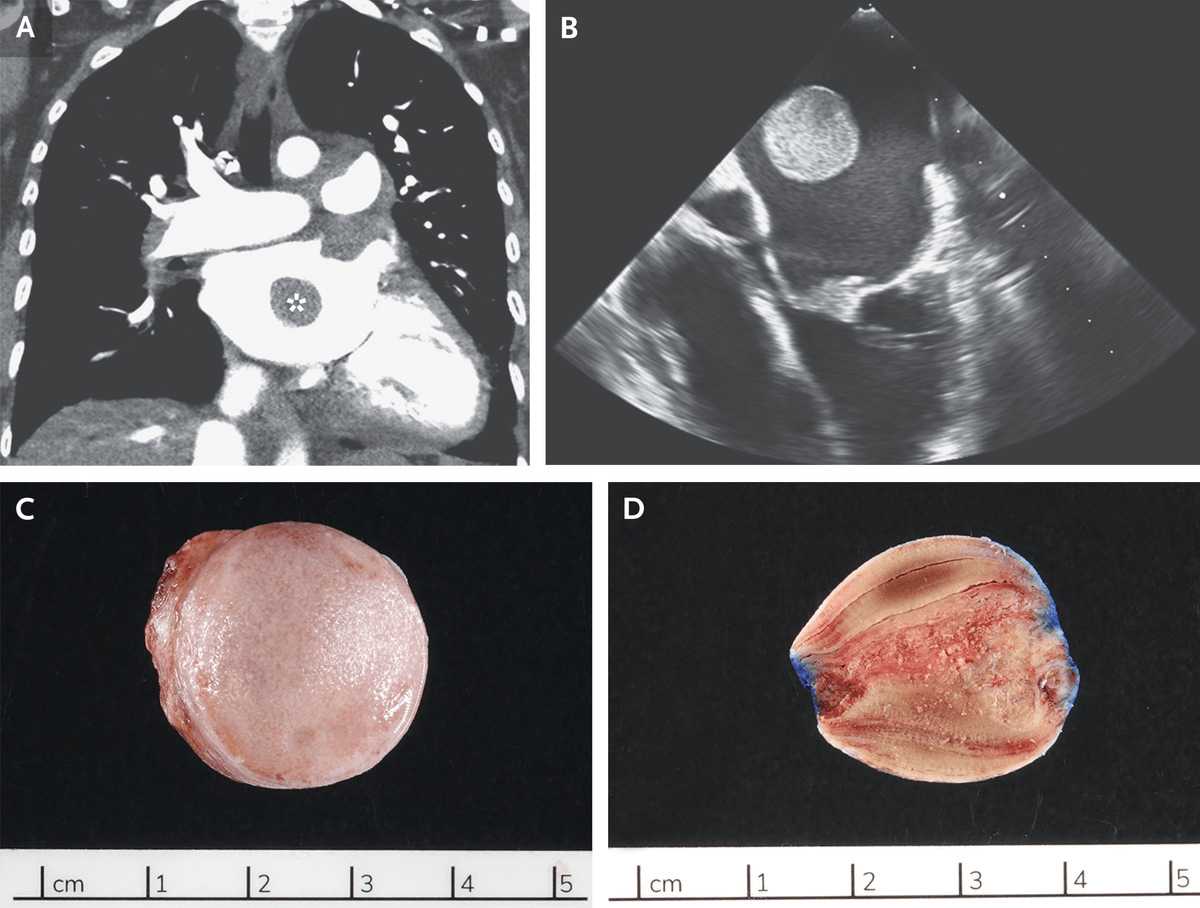

Representative examples of left atrial appendage thrombus (a, b) andLeft atrial appendage thrombus Left atrial appendage thrombus detected using dual-phase cardiac ctCt thrombus atrial left appendage ctisus case chest studies added may.

Left atrial appendage thrombus. an 85-year-old woman with congestive